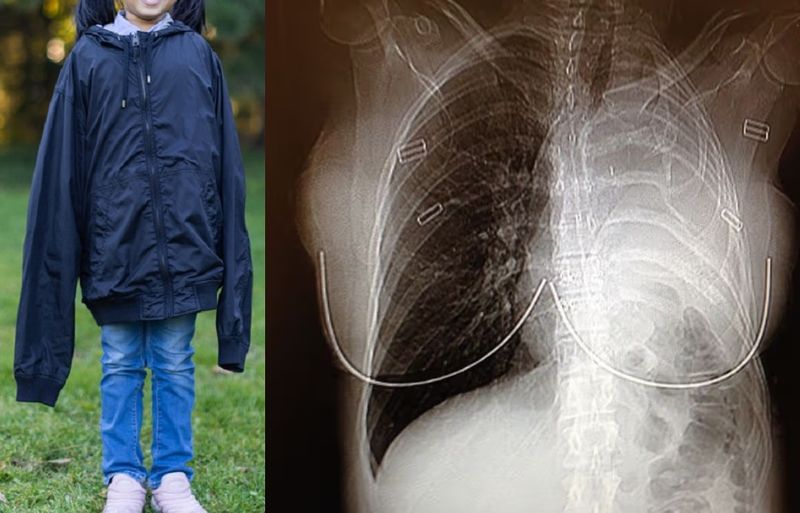

(서울=뉴스1) 박하나 기자 = 유튜버 히밥이 '아는 형님'에서 남다른 위 건강을 공개했다. 지난 28일 오후 방송된 JTBC 예능 프로그램 '아는 형님'에서는 '입으로 먹고살고(高)' 특집으로 꾸며져 테이, 히밥, 김신영, 송하빈이 출연해 입담을 뽐냈다. 남다른 대식가의 유튜버 히밥이 약 1000만 조회수를 기록한 '음식 랜덤 디펜스' 영상을 언급했다. 시청자들이 무작위로 보낸 음식을 6시간 동안 모두 먹어 없애며 생방송으로 중계했던 영상이라고. 이에 '디펜스 먹방 1짱'이라는 별명을 얻은 히밥의 먹방을 직관했던 테이는 "너무 신기하다, 음식을 진짜 마시는 것 같은 느낌이다"라고 감탄했다. 라면 25봉지 정도 먹어야 배부름을 느낀다는 히밥. 이어 히밥은 병원 검진을 받은 적이 있냐는 질문에 "공복일 때와 먹은 후의 위를 확인했는데, 위가 다른 장기를 다 밀어냈다, 신축성이 좋대"라고 답해 놀라움을 더했다. 어린 시절 동생의 모유까지 뺏어 먹을 정도로 타고난 대식가였다고. 위 건강을 자신한 히밥도 음식 때문에 입원한 경험이 있다고 밝혀 시선을 모았다. 히밥은 군대 인스턴트 음식 특집 먹방 후, 느린 소화에 병원에 5일간 입원했다고 해 모두를 놀라게 했다. 더불어 베이징대 사회학과 출신의 히밥은 충격적인 진로 변경에 어머니와 1년 동안 말을 하지 않았다고 고백했다. 그러나 히밥은 차를 선물한 이후 어머니께서 바로 인정했다고 해 웃음을 안겼다. 한편 히밥은 고수 같은 향이 강한 음식이나 갑각류를 선호하지 않는다고 밝혔다. 히밥은 "갑각류는 비효율적이다, 까는 동안 칼로리 소모가 엄청난 데 들어오는 게 없다, 먹는 데 배고프다"라고 전했다. JTBC '아는 형님'은 이성 상실 본능 충실 형님학교에서 벌어지는 토크쇼 프로그램으로 매주 토요일 오후 9시에 방송된다.